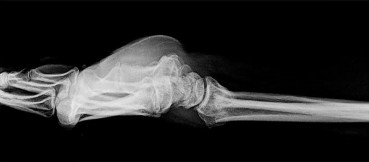

- الأشعة السينية (X-rays): هي الخطوة الأولى في تقييم الكسور، الخلوع، وتغيرات التهاب المفاصل. تساعد في تحديد مدى تدهور العظام والمسافات المفصلية. على سبيل المثال، تُظهر صور الأشعة السينية كسور السلاميات

. - الأشعة المقطعية (CT Scan): توفر صوراً تفصيلية ثلاثية الأبعاد للعظام، وهي مفيدة جداً لتقييم الكسور المعقدة، مثل كسور العظم الخطافي (Hamate Hook Fracture) التي قد لا تظهر في الأشعة السينية العادية

، أو لتقييم مدى تدهور العظم في حالات مثل مرض كينبوك. - التصوير بالرنين المغناطيسي (MRI): ممتاز لتقييم الأنسجة الرخوة مثل الأربطة، الأوتار، الأعصاب، والعضلات. يكشف عن التمزقات،